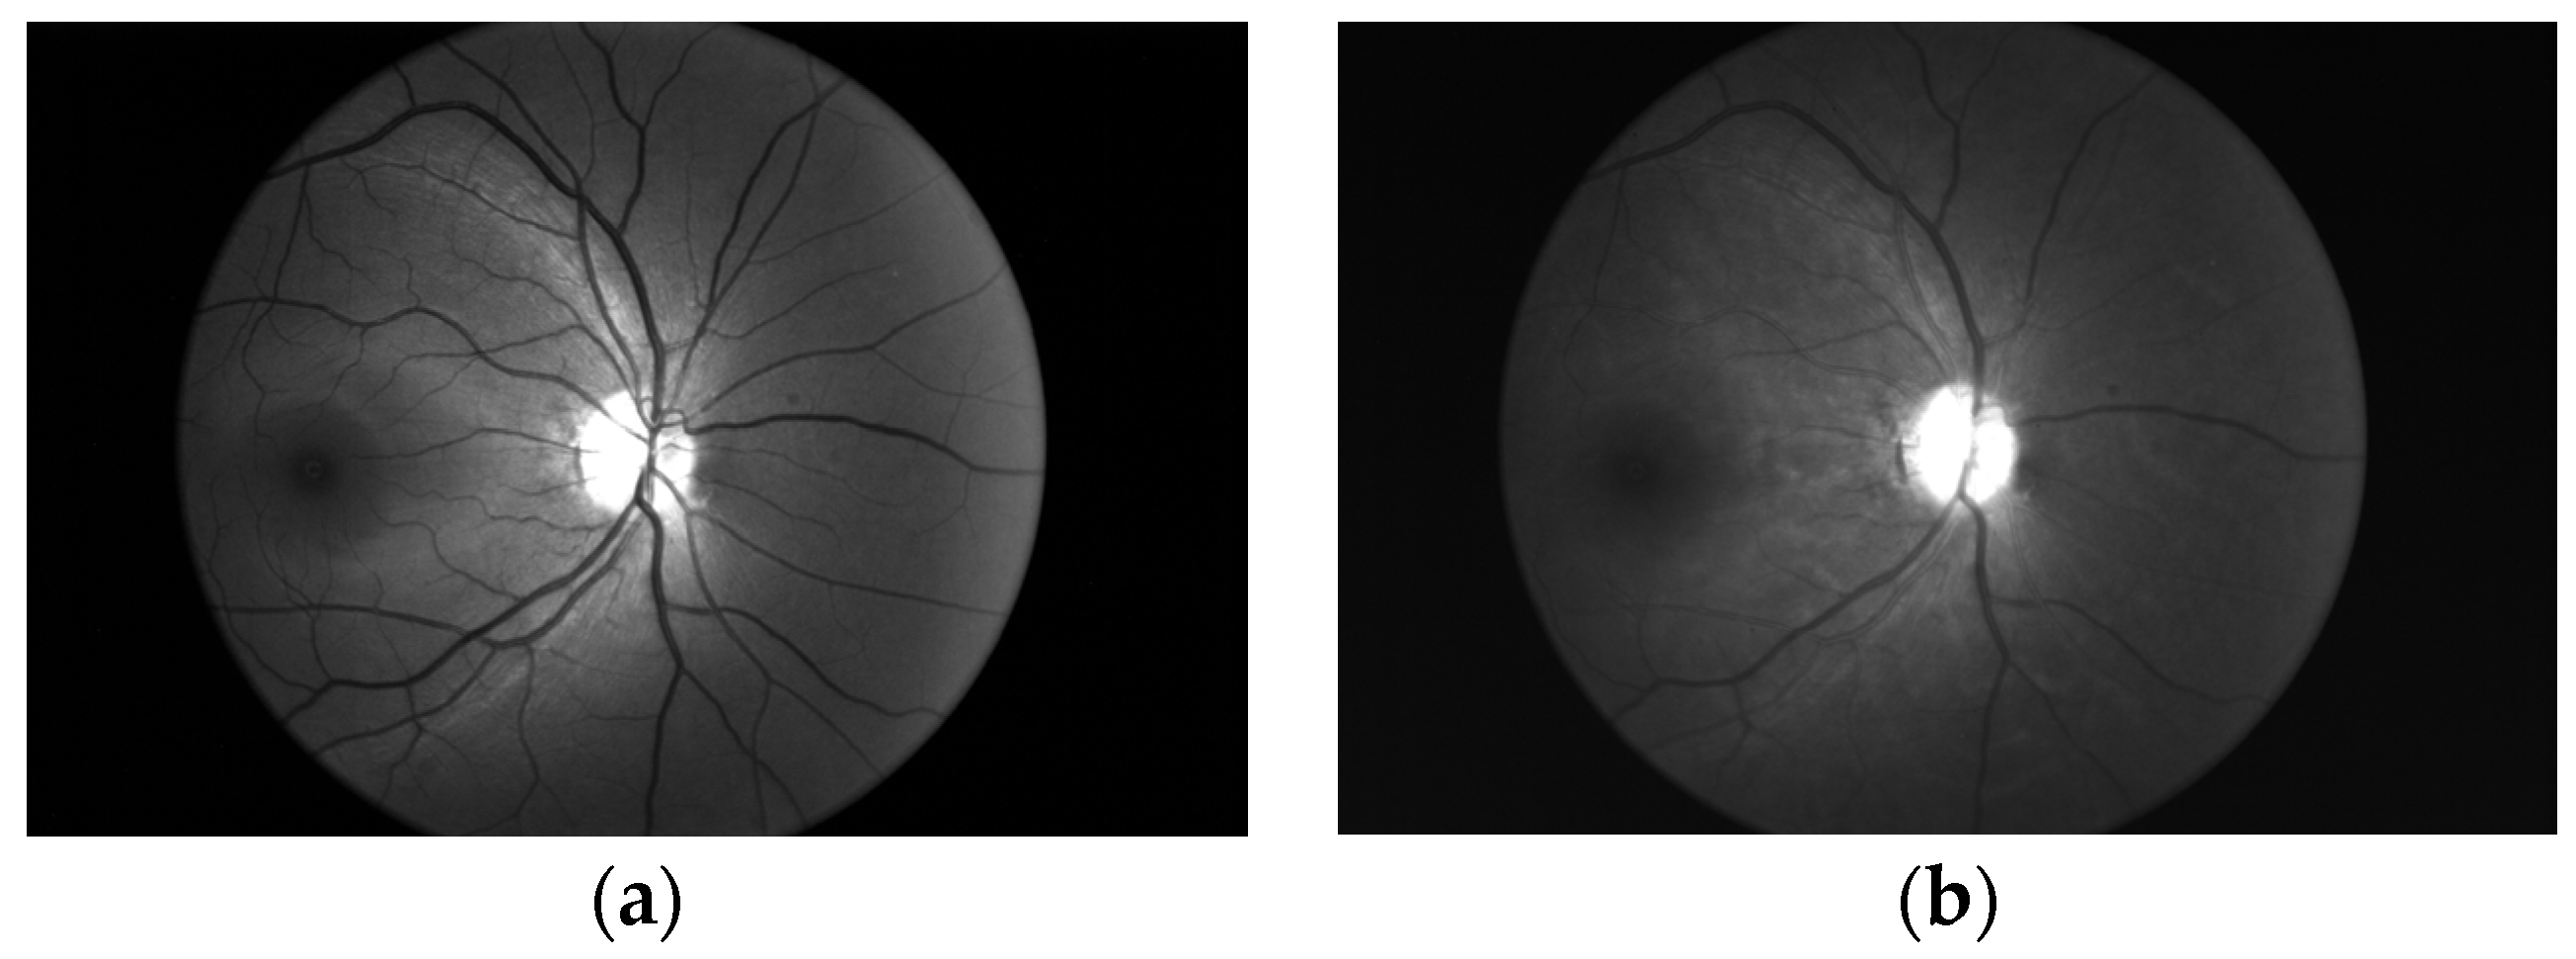

4.1. Comparison of Dual-Wavelength Retinal Image Segmentation Results